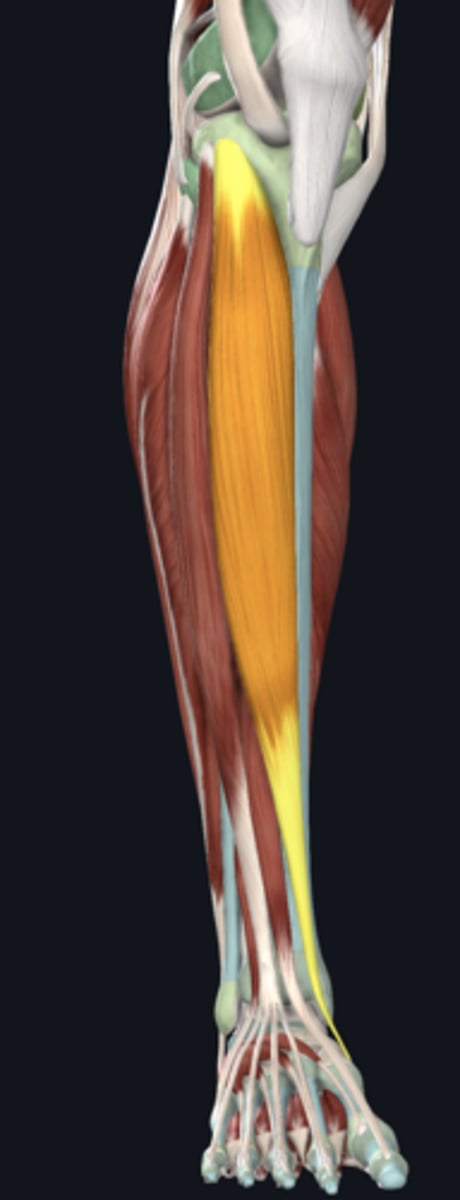

Tibialis anterior

Extensor digitorum longus

Extensor hallucis longus

Fibularis tertius muscle

Anterior tibial artery

Deep fibular nerve

nerve, deep

Superficial fibular nerve

nerve, superficial